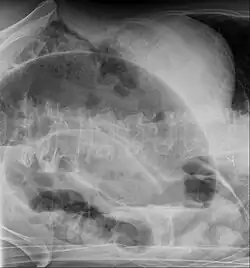

| Radiografia de abdomen mostrando um vôlvulo de sigmoide | |

A clínica é típica de abdômen agudo. O diagnóstico normalmente é feito com Raio-X (parece um balão radiolúcido ou com grãos de café) e tomografia computadorizada.